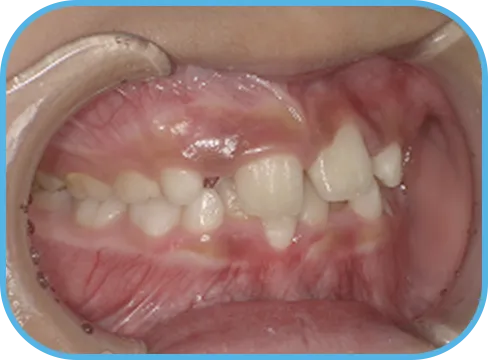

• Before

• 正 面

治療前正面からの歯の様子

• After

治療後正面からの歯の様子

主 訴

前歯がでている、噛み合わせが深い

治療内容

インビザライン・ファースト

治療期間

10か月

治療費(税別)

450,000円+診断料30,000円

リスク・副作用

• 親知らずの影響や加齢などによって、凸凹が生じる可能性があります。

• 治療の初期段階では痛みや不快感が生じやすくなりますが、1週間前後で慣れます。

• 顎の成長発育によって、噛み合わせや歯並びが変化する可能性があります。

• 状況により当初予定した治療計画を変更する可能性があります。